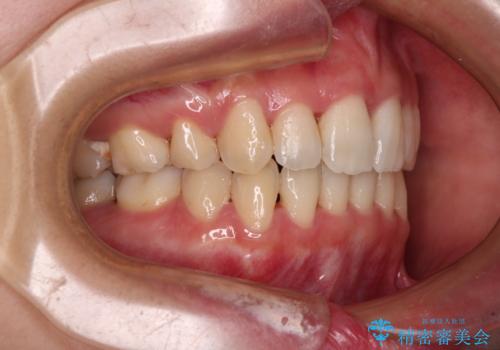

Eラインを改善したい ハーフリンガルによる抜歯矯正

- 3年6ヶ月

舌の突出癖が強く、口元を引っ込める力に拮抗してしまい、抜歯スペースを閉じるまでに時間がかかりました。

また途中出産もありましたが、無事に治療を終えることができました。